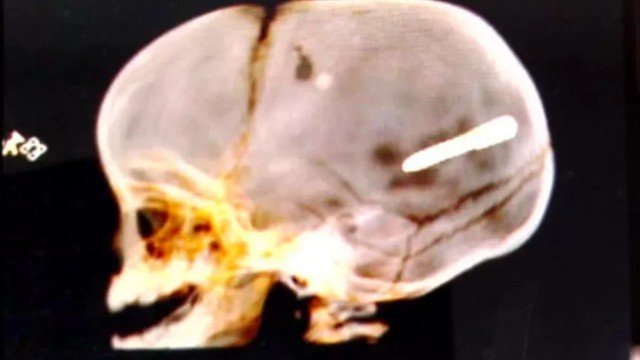

A Secretaria municipal de Saúde informou que Wallace havia passado por uma cirurgia mais cedo para reduzir pressão intracraniana. Não foi possível retirar o objeto, devido à área do cérebro atingida.